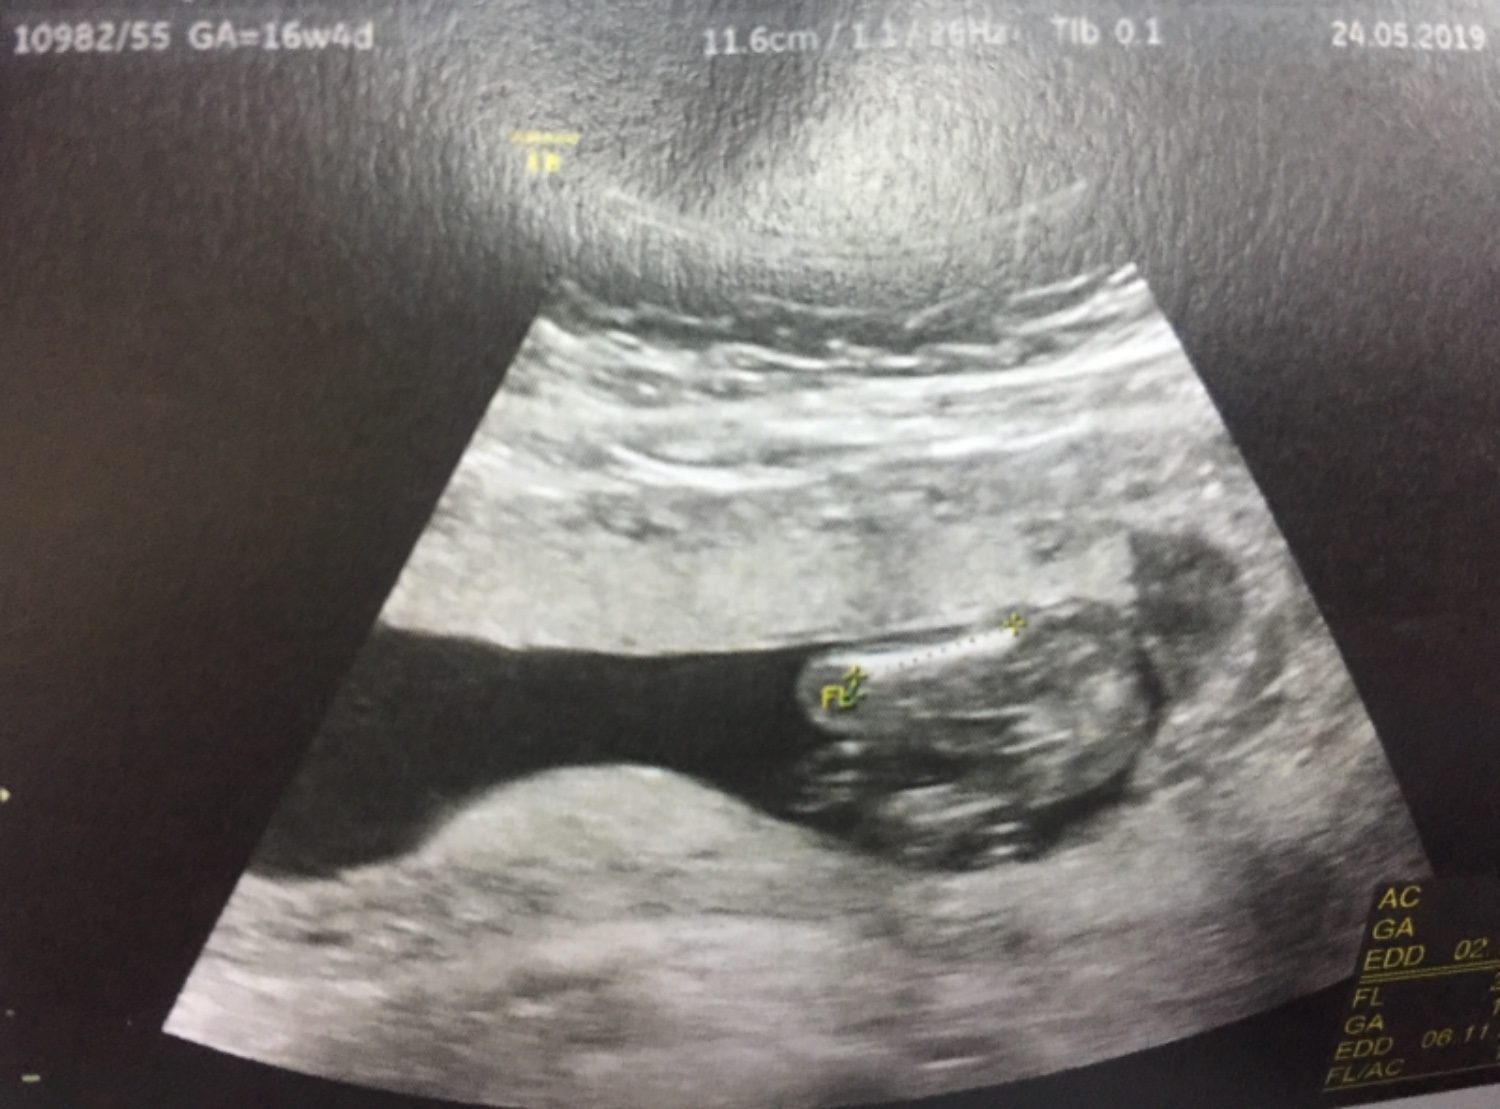

รบกวนคุณแม่ๆช่วยดูให้หน่อยค่ะ ว่าน้องเป็นเพศอะไร